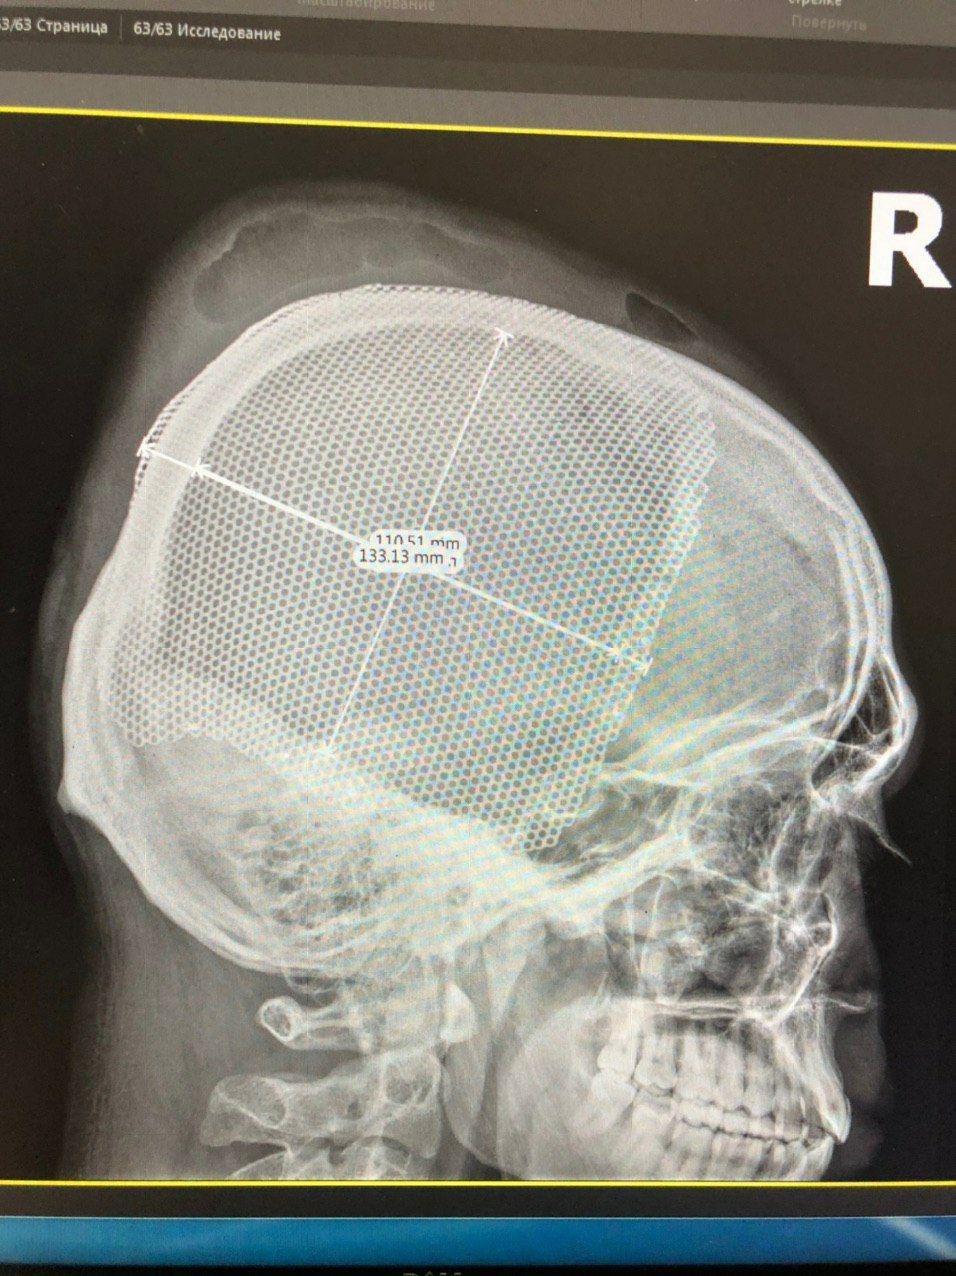

Владимир получил ранение 26 сентября 2019 года. Тогда его эвакуировали в больницу Мечникова на вертолете. "Состояние бойца было крайне тяжелым. Владимир сам не дышал, сердце почти не билось, давление приближалось к нулю, он находился в глубокой коме. Оказалось, пуля залетела под правый глаз, раздробила стенки гайморовой пазухи, пролетела все правое полушарие мозга, пробила затылочную кость и остановилась под кожей. Четыре с половиной часа длилась сложнейшая нейрохирургическая операция", - рассказал нейрохирург Александр Марченко. После первой операции бойца перевели на реабилитацию в военный госпиталь Киева. А позднее, 14 февраля, в больнице Мечникова ему провели пластику дефекта черепа и поставили титановую пластину.

"Последний день не помню. Вышло как-то нелогично, наверное, отрикошетила пуля и попала, к сожалению, в голову - это было практически невозможно. После первой операции мне возобновили целостность костей, еще долгое время была реабилитация. Когда уже была пластика, я полностью доверял врачу, так как до этого он провел титаническую работу. Так что, я думаю, пластика черепа для него не была большой проблемой. Меня все это время поддерживали родные, жена не подвела. Мы, кстати, поженились. Можно жить далее, даже с травмами, главное верить в себя", - рассказал Владимир.